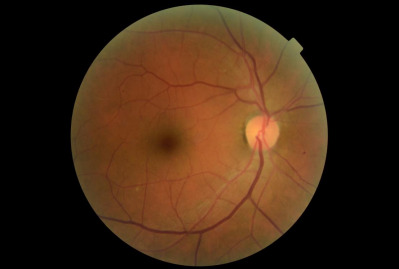

A dilated fundus examination was performed. The retina presented with a variety of diffuse hemorrhages varying from subhyaloid to intraretinal along with cotton wool spots and Rothspots in both eyes. The optic nerve presentation of each eye was normal and well perfused with no signs of abnormalities. At the completion of examination, the patient was diagnosed with an acute severe nongranulomatous anterior uveitis of the right eye and presumed severe non-proliferative diabetic retinopathy of both eyes. One year prior, the patient was seen for a comprehensive eye exam and was diagnosed with only mild nonproliferative diabetic retinopathy, see Images 1-4 for comparison.

Due to the severity of the anterior chamber reaction and the progression of the retinopathy, a full blood panel workup was ordered to determine if the findings were attributed to an infectious, inflammatory, or a neoplastic etiology. Differential diagnoses to consider for an acute nongranulamatous uveitis are conditions associated with human leukocyte antigen B27 (HLA-B27) such as, Reiter syndrome, inflammatory bowel disease including ulcerative colitis and Crohn’s disease, ankylosing spondylitis, Behcet disease and psoriatic arthritis. Other etiologies that can contribute to an acute nongranulomatous uveitis are lyme disease and acute trauma.4 Fundoscopic manifestations with marked hemorrhaging in the presence of Roth spots and cotton wool spots should be suspected for vascular and hematological abnormalities such as diabetes, leukemia, septic chorioretinitis secondary to bacterial endocarditis, anemia and sickle cell disease.4 This patient’s PCP was alerted to the ocular findings and possible concerns. Included in the blood panel orders (Table 1, reference 1 for abbreviations) were: a CBC with differential, ESR, CRP, ANA, ACE, RA, HLA-B27 and FTA-ABS.

Of all leukemia related ocular involvement, retinal involvement or leukemic retinopathy is the most common, occurring in 50-70% of patients.3,6 These posterior segment findings are typically a secondary or indirect manifestation resulting from tributary hematological abnormalities caused by the leukemia.5 Leukemia can cause secondary complications such as anemia, thrombocytopenia, hyperviscosities, etc .2,7 In the retina, these findings usually manifest as retinal vascular changes including intraretinal hemorrhages, cotton wool spots, white-centered hemorrhages or Roth spots, as well as vitreous hemorrhaging or vascular occlusions.3,8,9 The retina is the most involved ocular structure and it is estimated that nearly 70-90 percent of all patients diagnosed with leukemia will show fundus abnormalities at some point during their illness..3 Fundus findings are more prevalent in acute versus chronic leukemias and in myelogenous versus lymphocytic. Therefore, AML is associated with the highest occurrence of retinopathy.3 Abu el-Asrar et al. retrospectively evaluated the prognostic importance of retinopathy in adult and pediatric leukemia patients. They reported that the three-month mortality rate of patents with cotton-wool spots is eight times higher than in patients without these retinal lesions.3,10